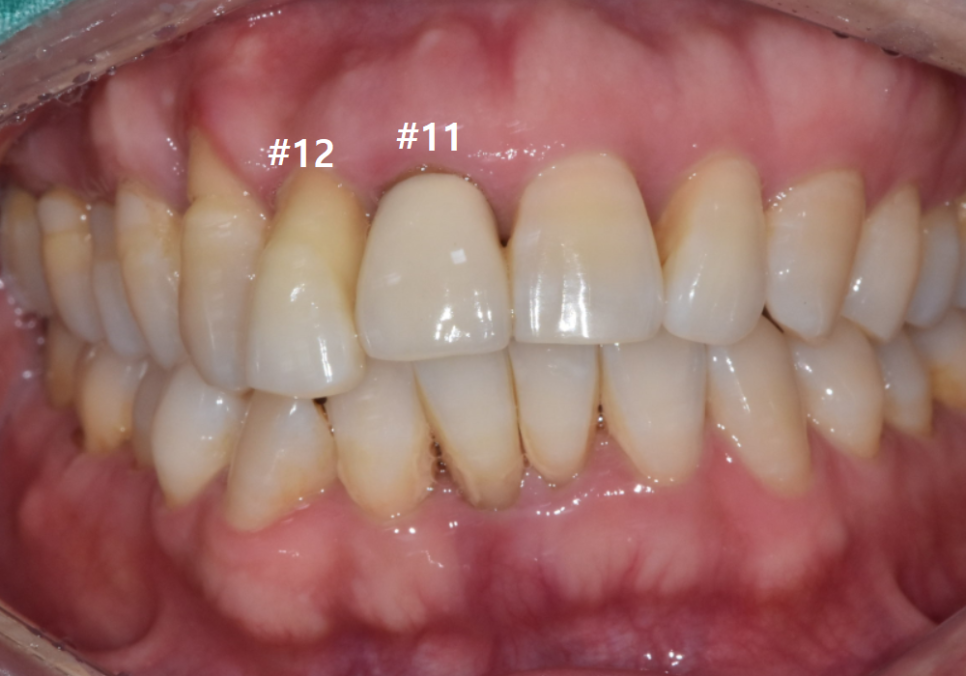

내원 당시 오른쪽 앞니(#12)가

심하게 흔들리고 있었고,

바로 옆 중앙 앞니(#11)도

잇몸뼈가 많이 내려가 영향을 받고 있었습니다.

240612

CT 분석 결과 중앙 앞니(#11) 치아 뿌리 끝에

염증이 발견되었지만,

환자분께서 최대한 자기 치아를

더 써보고 싶어 하셔서

일단 흔들림이 심한 오른쪽 앞니(#12)만

발치하고 임플란트를 진행했습니다.